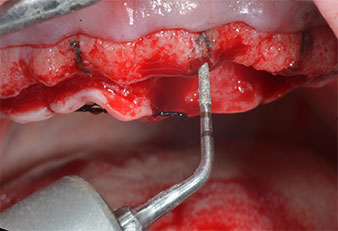

Para marcar las posiciones del implante y realizar la preparación piloto, se utilizó un inserto piezoeléctrico (Piezomed I1) con revestimiento de diamante y forma de llama (figura 3). Se tomaron precauciones para realizar movimientos hacia arriba y hacia abajo, con una potencia reducida, una irrigación completa y una baja presión (por debajo de 300 g). A continuación, se aplicó un inserto piloto (Piezomed I2A/I2P) para aumentar el diámetro inicial de 2 mm de los sitios de implante (figura 4), seguido de un inserto de 3 mm (Fig. 5).

Marcador ultrasónico Piezomed

Fig. 3: La preparación con inserto marcador ultrasónico Piezomed I1 se realizó con movimientos hacia arriba y hacia bajo, paralelos al eje longitudinal del área de trabajo.

Insertos Piezomed

Fig. 4: El siguiente paso fue el aumento piloto con los insertos I2A/I2P, que se aplicaron con un movimiento rotatorio horizontal.